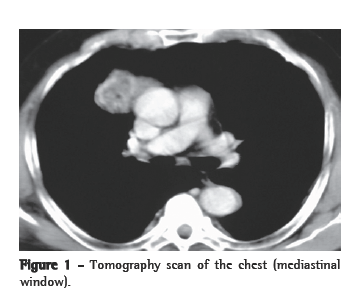

Case reportA 66-year-old male patient, born in the city of São Luiz (in the state of Maranhão) and a resident of the city of São Paulo (in the state of São Paulo), was admitted to the outpatient clinic presenting good general health status. The patient, who had no complaints, also had no history of morbidity or smoking. Radiological imaging, performed at another facility ten years prior, had revealed an anterior mediastinal tumor measuring approximately 4 cm in diameter. Therefore, we performed another round of chest X-rays and computed tomography scans of the chest. The new images revealed a tumor (3.0 × 4.0 cm) with spiculated margins, located in the right anterior mediastinum, with the same characteristics found on the scans performed previously (Figure 1). Laboratory test results and pulmonary function test results were normal. Tumors markers were normal. The syndromic diagnosis of anterior mediastinal tumor was confirmed, and surgical treatment was indicated.